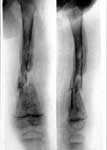

1.Гематогенный остеомелит левого бедра.

2.Последствия

остеомиелита.

3.Лечение в аппарате Илизарова.